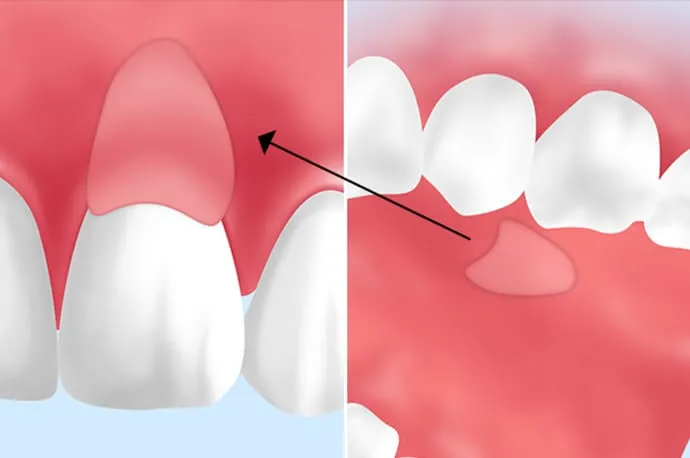

歯肉移植(歯ぐきの再生治療)とは

歯肉移植とは、下がってしまった歯ぐきを回復させるための治療です。

歯ぐきが下がると、次のようなお悩みが生じることがあります。

- 歯が長く見えてしまう

- 口元の見た目のバランスが崩れる

- 冷たいものがしみやすくなる

- セラミックや被せ物の境目が目立つ

といった問題が起こることがあります。

歯肉移植では、ご自身のお口の中(主に上あご)から健康な歯ぐきを採取し、下がってしまった部分に移植します。ご自身の組織を使用することで、自然で安定した歯ぐきの回復を目指します。

審美歯科における歯肉移植の重要性

審美歯科治療では、歯の色や形だけでなく、歯ぐきとの調和がとても重要です。歯ぐきが下がったままの状態では、どれほど美しいセラミックを装着しても、不自然な印象になることがあります。

歯肉移植を行うことで、- 歯と歯ぐきのバランスが整う

- 歯の見える長さが自然になる

など、より完成度の高い審美治療につながります。